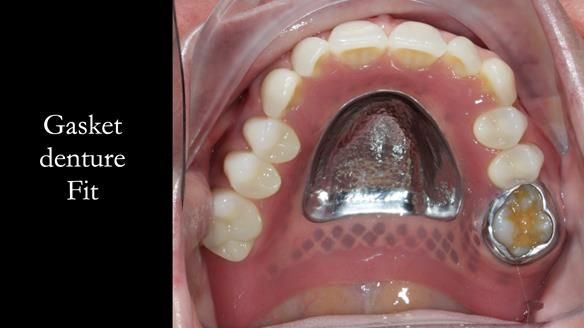

Welcome to my Newsletter 58, where I show the making and fitting of an upper gasket partial denture for Zoe (52 year old woman). This issue provides a comprehensive overview of the entire protocol workflow for this superbly retained denture.

The detailed clinical situation and treatment process are outlined below, with clinical work provided by me and technical work by Rowan Garstang. The treatment spanned five visits for denture fitting and one review.